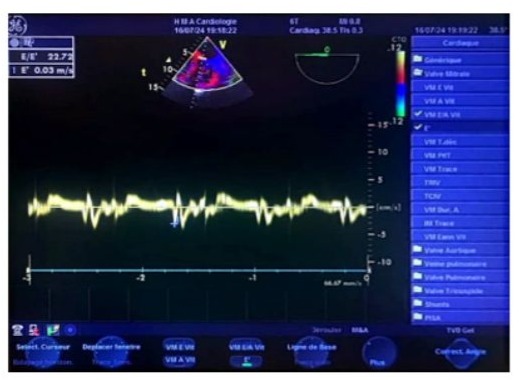

Left ventricular filling pressures were normal, and the inferior vena cava was dilated to 16 mm and slightly compliant. (Figure 3,4) The left atrium was dilated, with a surface area of 21.5 cm² and a volume of 44 ml/m². (Figure 5) The right ventricle had preserved systolic function with a TAPSE (Tricuspid Annular Plane Systolic Excursion) of 22 mm and a tissue Doppler S’ velocity of 12 cm/s. The right atrium was dilated at 19.7 cm², free of echoes. Assessment of the valvular apparatus showed a tricuspid aortic valve with degenerative changes, including calcified masses between the right and left cusps, limiting valve opening. Severe stenosis was noted, with a valvular area of 0.8 cm² (indexed area of 0.58 cm²), a Vmax of 3.93 m/s, and a mean gradient of 35 mmHg. The aortic annulus measured 19 mm, and minimal regurgitation was observed. (Figure 6-9)

Figure 4: Tissue Doppler imaging (TDI) at the mitral annulus was performed using a 4-chamber view, minimizing filters and gains, and placing the sampling window at the lateral annulus (A) or the septal annulus (B). The TDI recording showed a positive systolic wave followed by a single diastolic Ea wave at 7 cm/s lateral, (A) and 11 cm/s septal, (B), with no Aa wave due to atrial fibrillation. The absence of significant reduction in the Ea wave indicates normal flow, as in healthy individuals, the Ea wave is typically greater than 8 cm/s